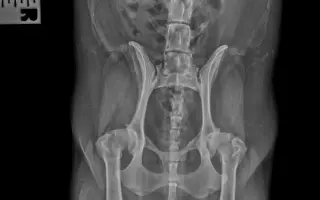

Fotogalerie